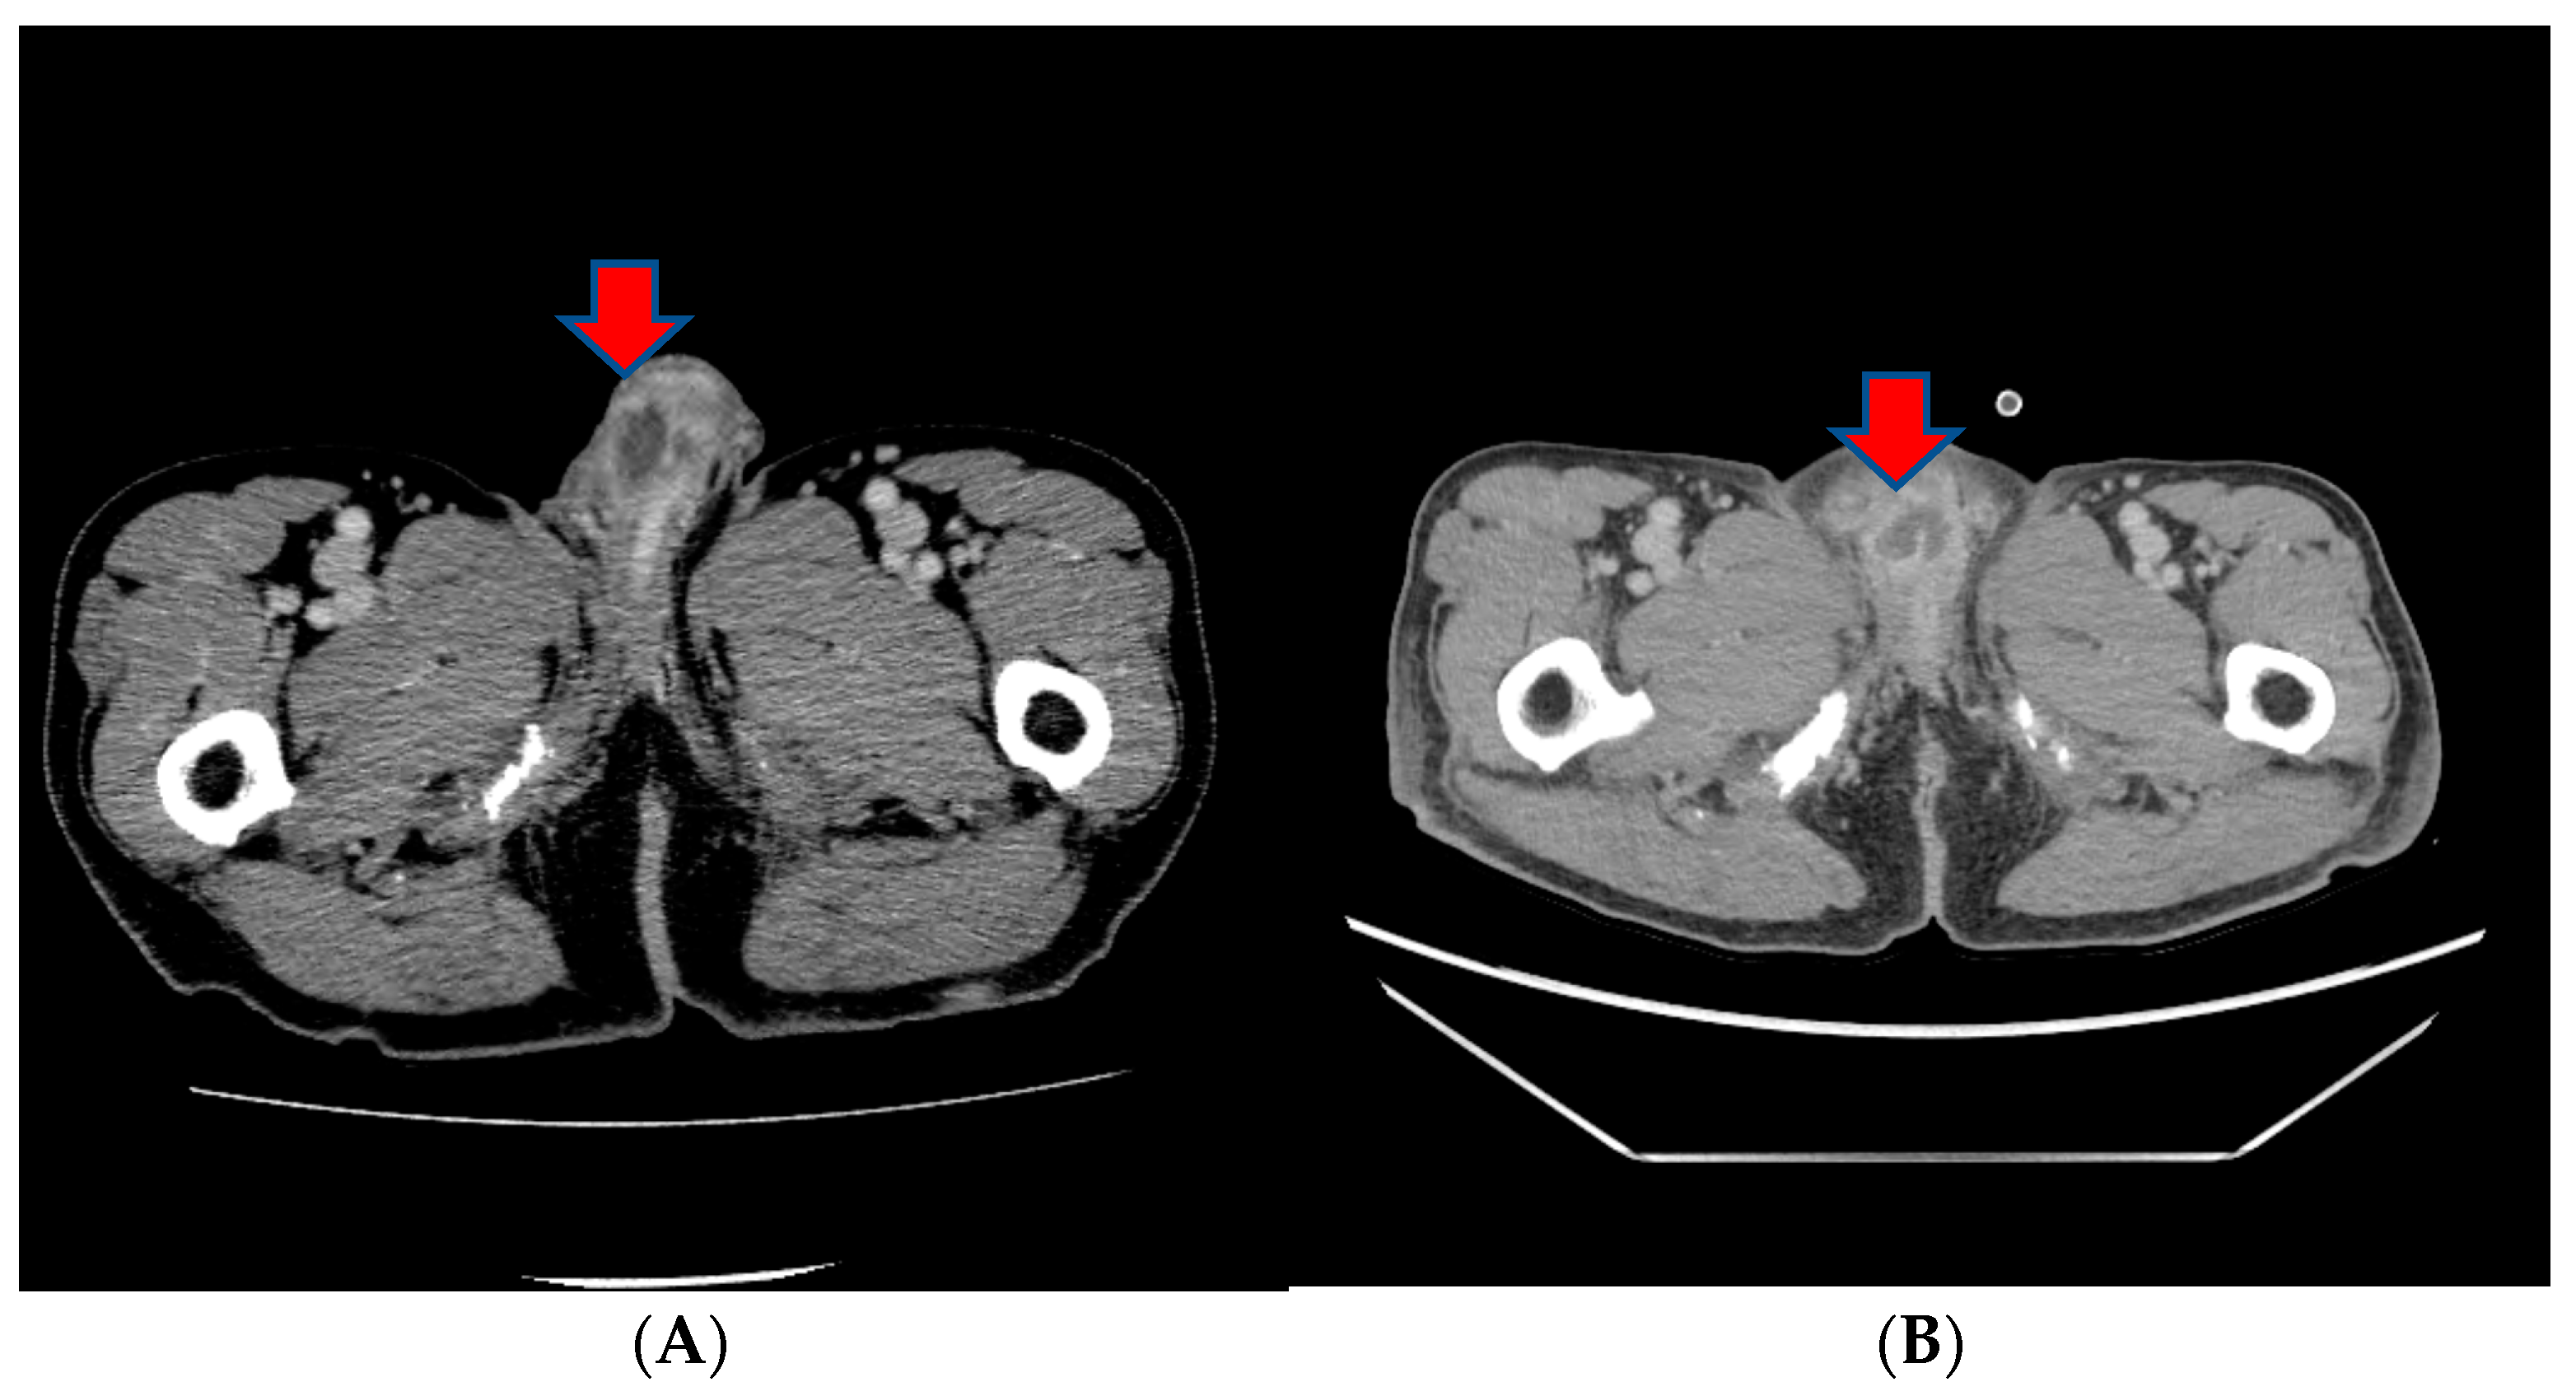

About a month after the surgical procedure, the patient began experiencing penile discomfort, which worsened over three months, prompting his hospital visit. Upon physical examination, a palpable mass was detected at the penoscrotal junction of the penis. The mass was tender, firm in consistency without ulcerations or rash, and measured approximately 5 cm in diameter. No other abnormalities were noted during the examination of the genitalia. Subsequent to this, a CT scan revealed an irregularly shaped enhancing mass in the penis, suggesting the possibility of metastasis (Figure 3). Laboratory results were within normal ranges. On urinalysis, pyuria was observed, but the urine culture showed no microorganism. Magnetic resonance imaging (MRI) findings revealed a lobulated contour and heterogeneously enhanced mass-like lesion in the corpus cavernosa of the penis on T2-weighted images, which raised the possibility of metastasis (Figure 3). A PET-CT showed an irregular increased fludeoxyglucose (FDG) uptake in the penis (Figure 3).

Figure 3.

(A) An irregularly shaped enhancing mass in the penis on CT scan. (B) Magnetic resonance imaging (MRI) findings showing a heterogeneously enhanced mass-like lesion in the corpus cavernosa of the penis on T2-weighted images. (C,D) PET-CT showing an irregular increased fludeoxyglucose (FDG) uptake in the penis.